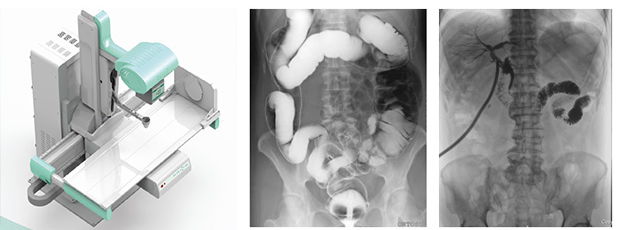

近年來,DR設(shè)備正朝著更加準(zhǔn)確化、輕便化、智能化和多維化方向發(fā)展,出現(xiàn)了多功能動(dòng)態(tài)DR、移動(dòng)DR、三維化DR產(chǎn)品等等。其中多功能動(dòng)態(tài)DR大大提高了普通放射設(shè)備準(zhǔn)確診斷的能力,為臨床創(chuàng)造了價(jià)值。接下來給大家分析下多功能動(dòng)態(tài)DR是如何提高工作效率的。以下是部分體位介紹及解決方案:

在這些對(duì)球管中心線和受檢部位形成角度有要求的體位的擺位過程中,可以應(yīng)用多功能動(dòng)態(tài)DR的電動(dòng)控制擺臂、數(shù)字顯示角度值和動(dòng)態(tài)透視影像觀察功能等特性,使這些體位的擺位更加準(zhǔn)確、讓醫(yī)生工作效率更高!如果您想采購普愛醫(yī)療的多功能動(dòng)態(tài)DR,或了解產(chǎn)品技術(shù)參數(shù),歡迎聯(lián)系我們。